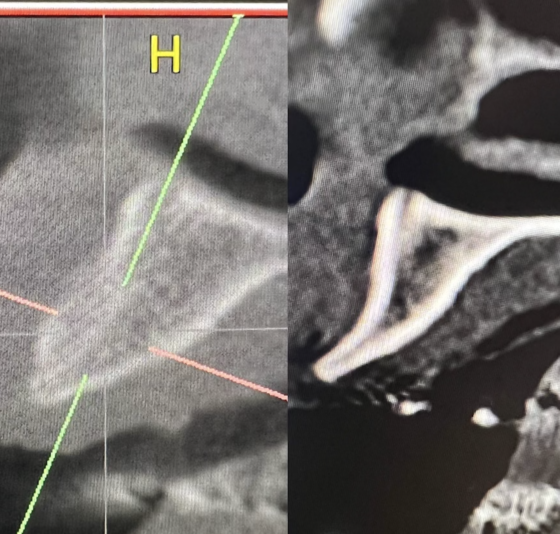

Hey guys just wanted to get to know your thoughts on what I can do to improve. This is a 78 yr old patient with controlled diabetes/hypothyroid/high BP. She takes her medications regularly and reports to be controlled. #29 was extracted due to fracture in October 2022 with bone graft. Implant Astra Osseospeed EV size 3.6×9 was placed in…

I created a deeper osteotomy today and placed a larger longer implant after removing the failed implant and thoroughly curetting and irrigating with CHX. Any guidance and feedback is welcome.